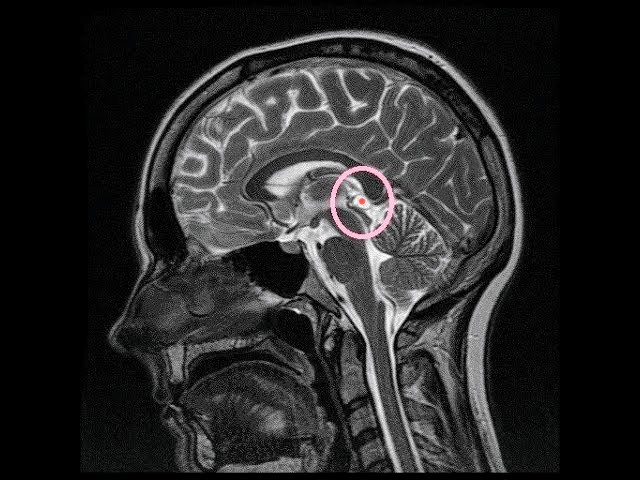

Шишковидная железа — это крошечный орган в центре мозга, всего 1–3 мм, но он управляет ключевыми процессами в теле и психике… если она работает.

Египтяне изображали её в виде глаза Гора — это срез мозга, где виден лимбический центр и шишковидная железа.